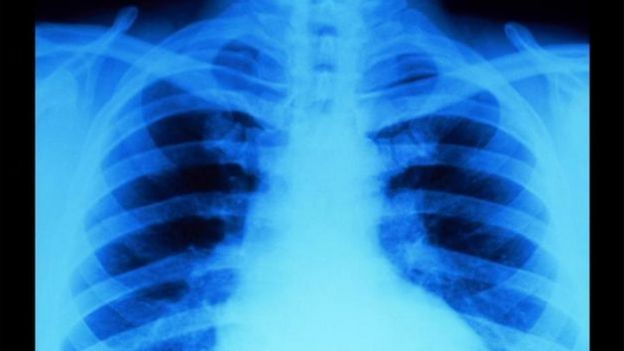

Após o nascimento, é possível fazer uma radiografia do bebê para avaliar em que medida há danos generalizados nos ossos, mas a confirmação ou esclarecimento do diagnóstico vêm com uma análise genética.